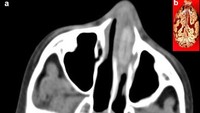

Dokter menemukan biji jarak tersangkut di rongga hidung seorang bocah 7 tahun. Bocah itu awalnya mengalami mimisan satu hari sampai akhirnya dibawa ke rumah sakit. (Foto: F1000 Research)